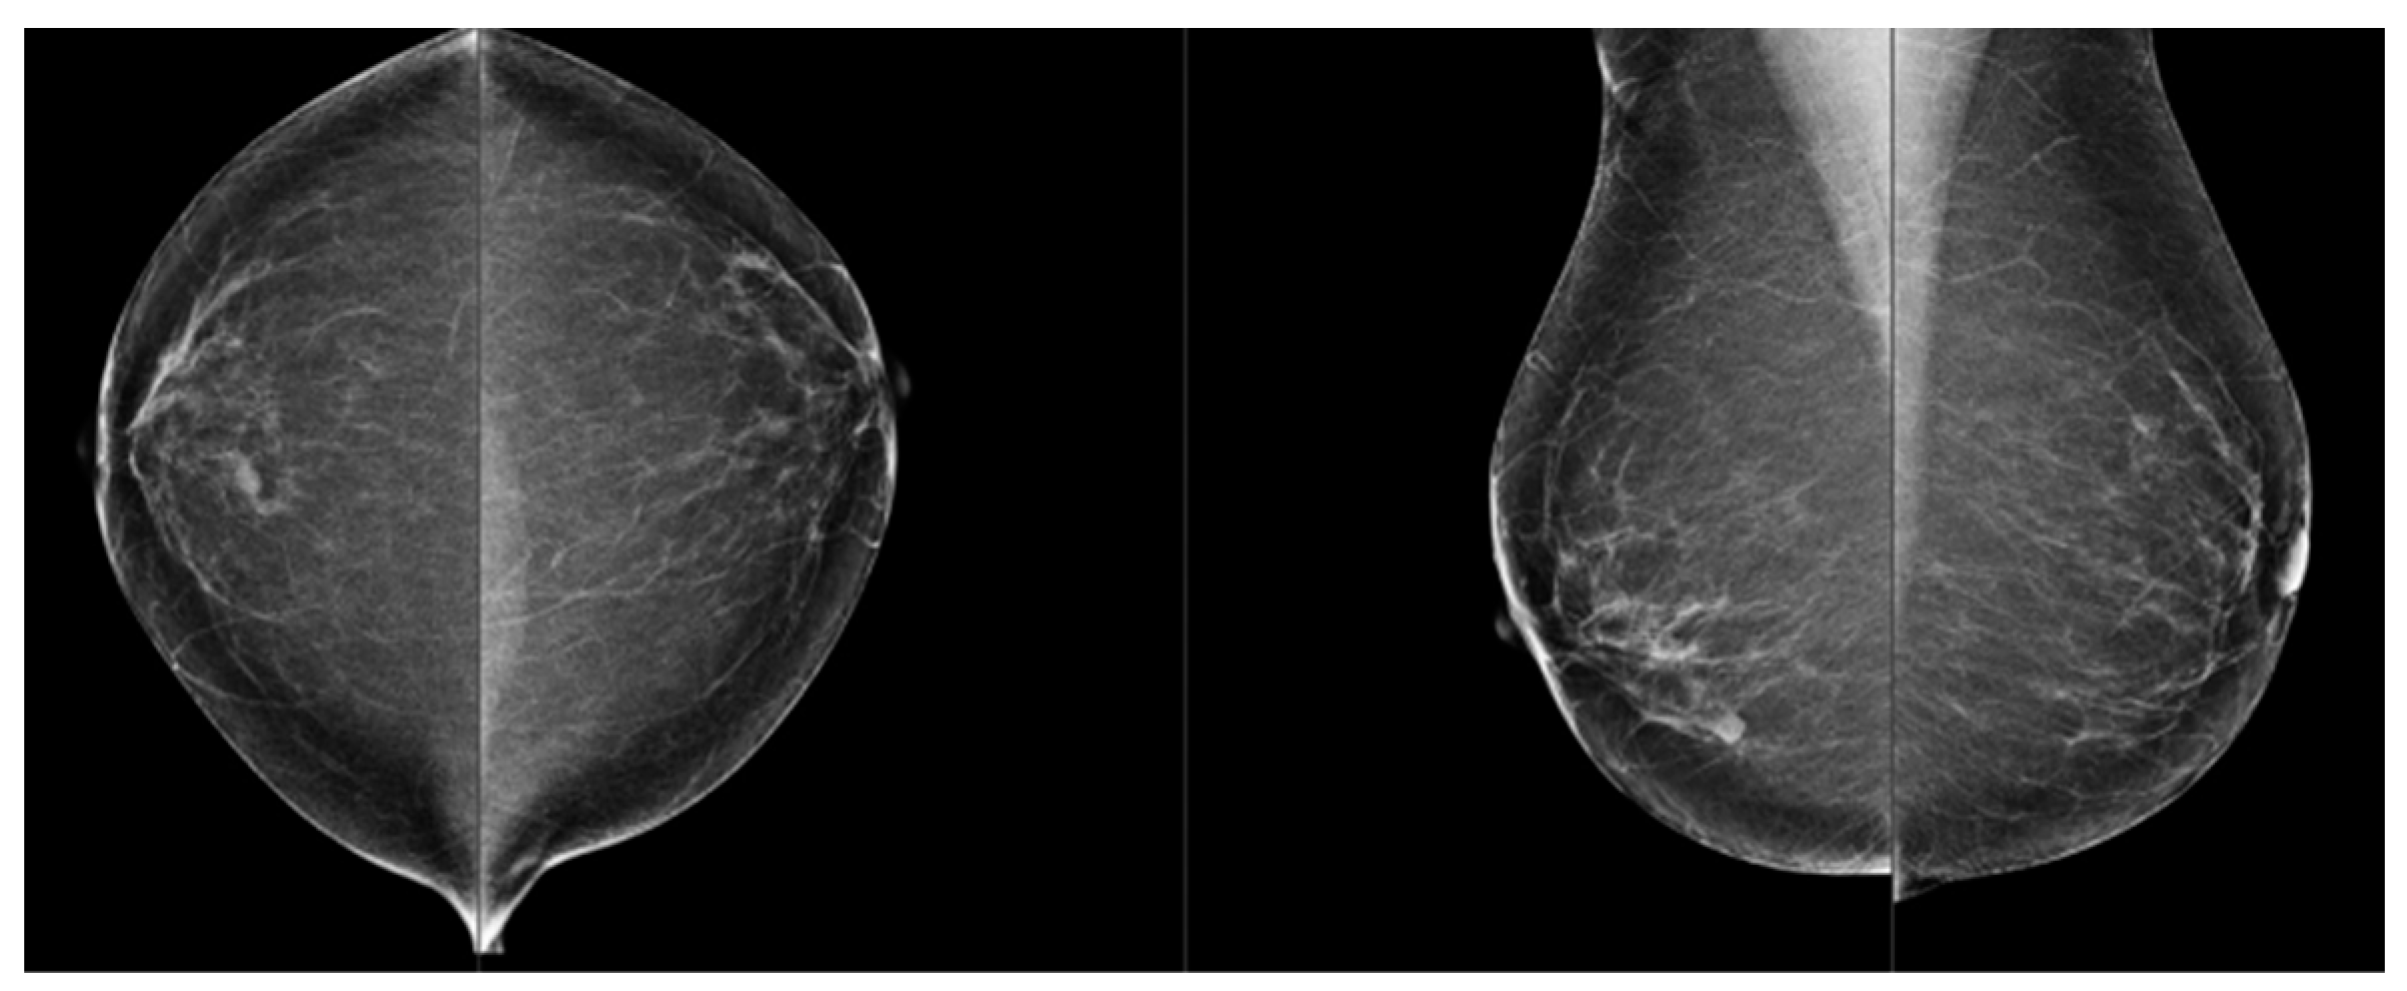

Comparison of Visual and Quantra Software Mammographic Density Assessment According to BI-RADS® in 2D and 3D Images

2. Materials and Methods

2.2. Image Acquisition

2.3. Software for Automatic Breast Density Assessment